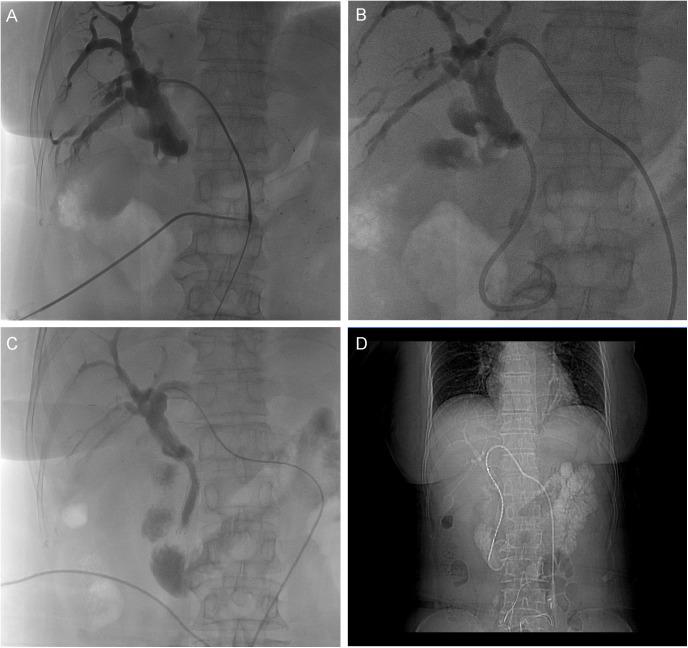

Malignant obstructive jaundice (MOJ) due to tumor compression or invasion of the bile duct carries a grave prognosis. We report a case of a 54-year-old female patient (height: 160 cm, weight: 55 kg, BMI: 21.5 kg/m², ECOG performance status: 1, with type 2 diabetes mellitus) advanced pancreatic head cancer causing MOJ, managed with a multidisciplinary approach. Initial endoscopic retrograde cholangiopancreatography (ERCP) with an 8.5 Fr plastic stent failed due to occlusion after 20 days, leading to bilirubin rebound. Emergency percutaneous transhepatic cholangial drainage (PTCD) followed by biliary metal stent (8 mm × 80 mm) and iodine-125 seed implantation effectively relieved obstruction, reducing total bilirubin (TBIL) from 116.9 to 45.6 μmol/L within seven days. Subsequent tomotherapy (TOMO, 66 Gy to gross tumor volume) and a personalized regimen of S1 (tegafur, 20 mg/day), nimotuzumab, and pembrolizumab, following intolerance to gemcitabine + nab-paclitaxel (AG), achieved a 78% reduction in CA19-9 and sustained biliary patency. At one-year follow-up, TBIL was 18.2 μmol/L, direct bilirubin (DBIL) was 9.8 μmol/L, and the patient reported a good quality of life (Karnofsky score: 90). This case demonstrates the efficacy of sequential PTCD, seed stent, and targeted-immunotherapy, offering a practical model for managing advanced pancreatic cancer with MOJ.

因肿瘤压迫或侵犯胆管导致的恶性梗阻性黄疸(MOJ)预后严重。我们报告一例54岁女性患者(身高:160 cm,体重:55 kg,BMI:21.5 kg/m²,东部肿瘤协作组体能状态:1,患有2型糖尿病),其晚期胰头癌导致MOJ,采用多学科方法进行治疗。最初的内镜逆行胰胆管造影(ERCP)置入8.5 Fr塑料支架,20天后因堵塞失败,导致胆红素反弹。紧急经皮经肝胆管引流(PTCD),随后置入胆道金属支架(8 mm×80 mm)并植入碘-125粒子,有效缓解了梗阻,7天内总胆红素(TBIL)从116.9降至45.6 μmol/L。随后进行断层放疗(TOMO,肿瘤总体积给予66 Gy),以及在患者对吉西他滨+纳米白蛋白结合型紫杉醇(AG)不耐受后采用的S1(替加氟,20 mg/天)、尼妥珠单抗和帕博利珠单抗个体化方案,使CA19-9降低了78%,并维持了胆道通畅。在一年的随访中,TBIL为18.2 μmol/L,直接胆红素(DBIL)为9.8 μmol/L,患者报告生活质量良好(卡诺夫斯基评分:90)。该病例证明了序贯PTCD、粒子支架和靶向免疫治疗的疗效,为晚期胰腺癌合并MOJ的管理提供了一个实用模型。